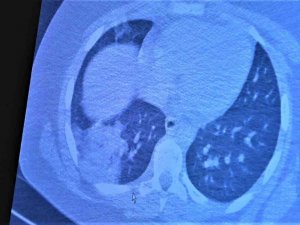

Koronaya yakalanan 15 yaş altı çocuklarda ciddi akciğer tutulumları

Covid-19 inme, beyin kanaması ve böbreklerde hasar bırakabiliyor

Türkiye’nin ilk Covid-19 Takip Merkezi’ne başvuran hastaların ortak şikayeti ‘nefes darlığı’